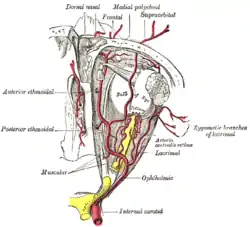

Anterior cerebral circulation

The anterior cerebral circulation is the blood supply to the anterior portion of the brain including eyes. It is supplied by the following arteries:

- Internal carotid arteries: These large arteries are the medial branches of the common carotid arteries which enter the skull, as opposed to the external carotid branches which supply the facial tissues; the internal carotid artery branches into the anterior cerebral artery and continues to form the middle cerebral artery. [4]

- Anterior cerebral artery (ACA)

- Anterior communicating artery: Connects both anterior cerebral arteries, within and along the floor of the cerebral vault.

- Middle cerebral artery (MCA)